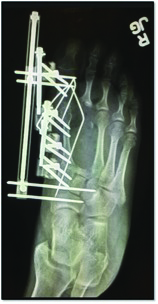

Bone transport/distraction osteogenesis is another modality that one can utilize for non-union, avascular necrosis or segmental bone loss from infection. In Mather’s study, 15.8 weeks were required to achieve 93.8 percent length and consolidation of the second metatarsal.43 Benson and coworkers showed results averaging 20.2 mm in length of callus distraction when using bone transport.41

While the technique and use of bone transport can provide success while keeping the first ray out to an appropriate length, one must be mindful of the soft tissue envelope and the lack of intrinsic musculature when performing this procedure. It is also important to base the vector of transport to the distal pins and lengthen parallel to the ground to avoid metatarsus primus equinus. We recommend preserving the metatarsal parabola (approximately 142 degrees with the first metatarsal equal to the third metatarsal). Consider bone transport procedures in two stages on the first metatarsal due to the likely requirement to fuse the distal regenerate bone with the base of the proximal phalanx. In keeping with principles of bone transport and tibialization of the fibula, one can also perform gradual transverse medialization of the second metatarsal and docking with the medial cuneiform and proximal phalanx successfully. Authors have described fibular bone hypertrophy occurring over the course of five years and it is therefore plausible for the second metatarsal to hypertrophy as well.44,45